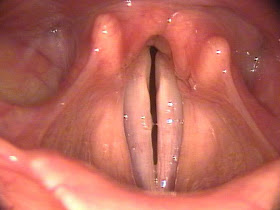

Bilateral Vocal Cord Paralysis:

In contrast to unilateral vocal cord paralysis, voice quality is not the primary concern in patients with bilateral vocal cord paralysis. The significant problem is airway compromise. This can range from unnoticeable to, more commonly, dyspnea and stridor. The patient's voice quality is usually only mildly affected (if just the recurrent laryngeal nerves are invulved) because the paralyzed cords tend to assume the natural position for phonation.